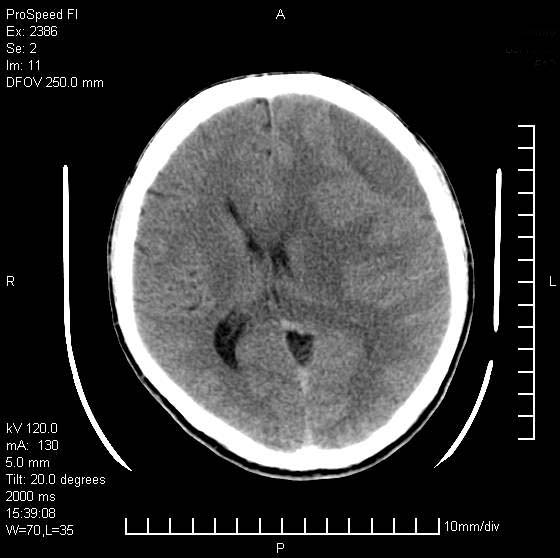

以下是引用天南地北在2007-9-19 18:43:00的发言:[br]典型慢性硬膜外血肿[br][br][本贴已被 天南地北 于 2007-9-19 18:44:11 修改过]

以下是引用曼一拍在2007-9-20 11:06:00的发言:[br]支持慢性硬膜下血肿.[br]慢性硬膜下积液:血肿有包膜,ct值稍高于脑脊液,增强可有染色。不典型者血肿可多呈梭形.是硬脑膜与蛛网膜之间的潜在腔隙内的血肿。[br]鉴别:[br]1\\硬膜外血肿:是颅脑外伤后脑膜或板障内血管破裂,血液在颅骨与硬膜之间积聚所致.通常是脑膜动脉破裂,也可因静脉窦破裂或颅骨的板障静脉出血,发生于外伤的着力部,常与颅骨骨折并存。脑膜动脉出血则急,若是板障静脉出血在则可有慢性。[br]2\\硬膜下积液:(硬膜下水瘤)[br]是由于蛛网膜破裂,脑脊液经蛛网膜破口进入硬膜下腔不能回流。或水肿阻塞而形成。[br]ct表现:颅骨内板下方新月形低密度区近似脑脊液密度;占位效应清,周围无脑水肿。[br]